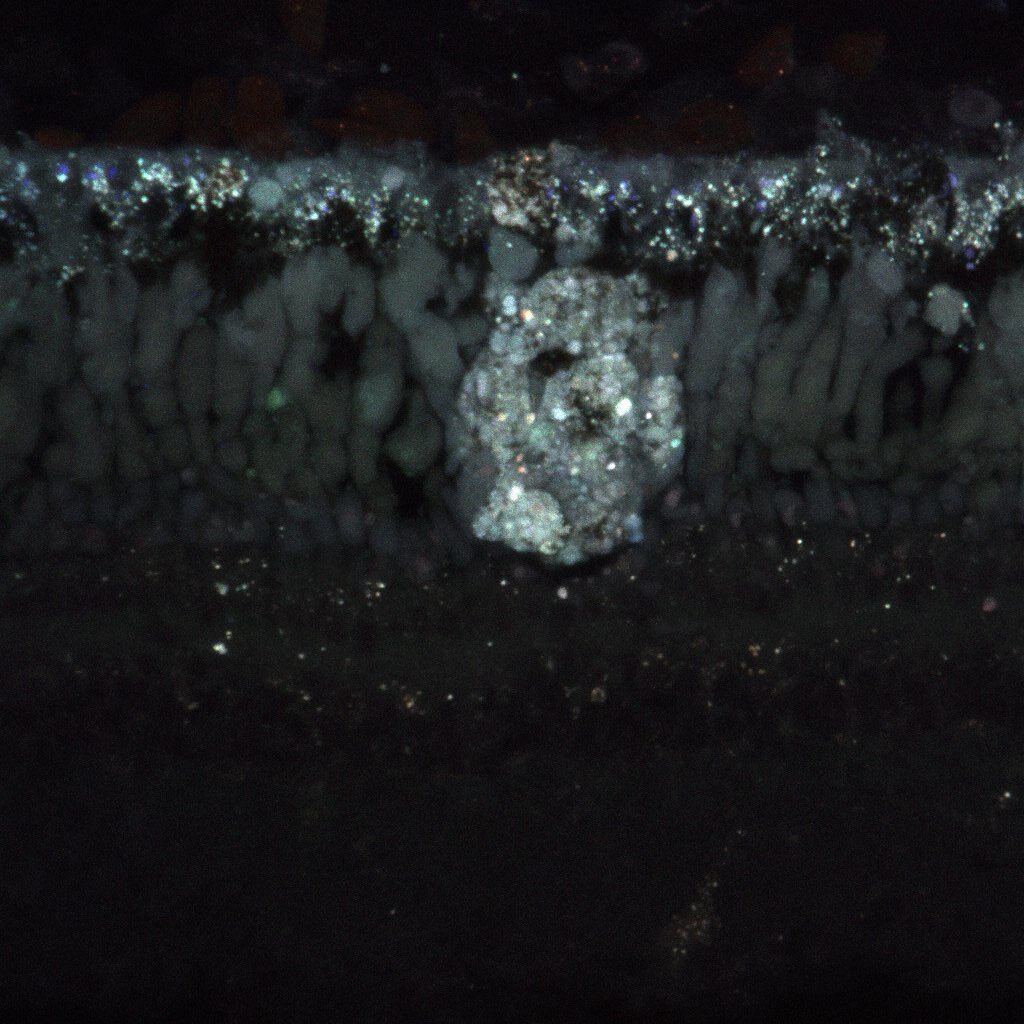

A frog eye with a very large deposit of cellular debris, the target of Dr. Carr’s research.

Dr. Carr’s new model focuses on frogs, which also develop debris in their retinas as they age. Her method uses CRISPR gene-editing technology, a technique that allows scientists to make precise modifications to DNA. By probing a gene that is also important in human vision loss, Dr. Carr can investigate the origin point for cellular debris related to AMD.